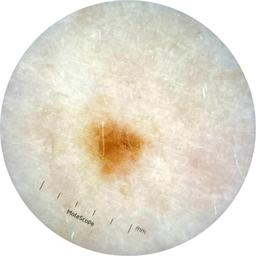

ISIC_9785574

2003 x 2003

Field Value

acquisition_day 148

age_approx 45

anatom_site_1 Head and neck

anatom_site_general head/neck

concomitant_biopsy False

diagnosis_1 Benign

diagnosis_confirm_type single image expert consensus

family_hx_mm True

image_manipulation instrument only

image_type dermoscopic

lesion_id IL_0236417

patient_id IP_8456088

personal_hx_mm True

sex female